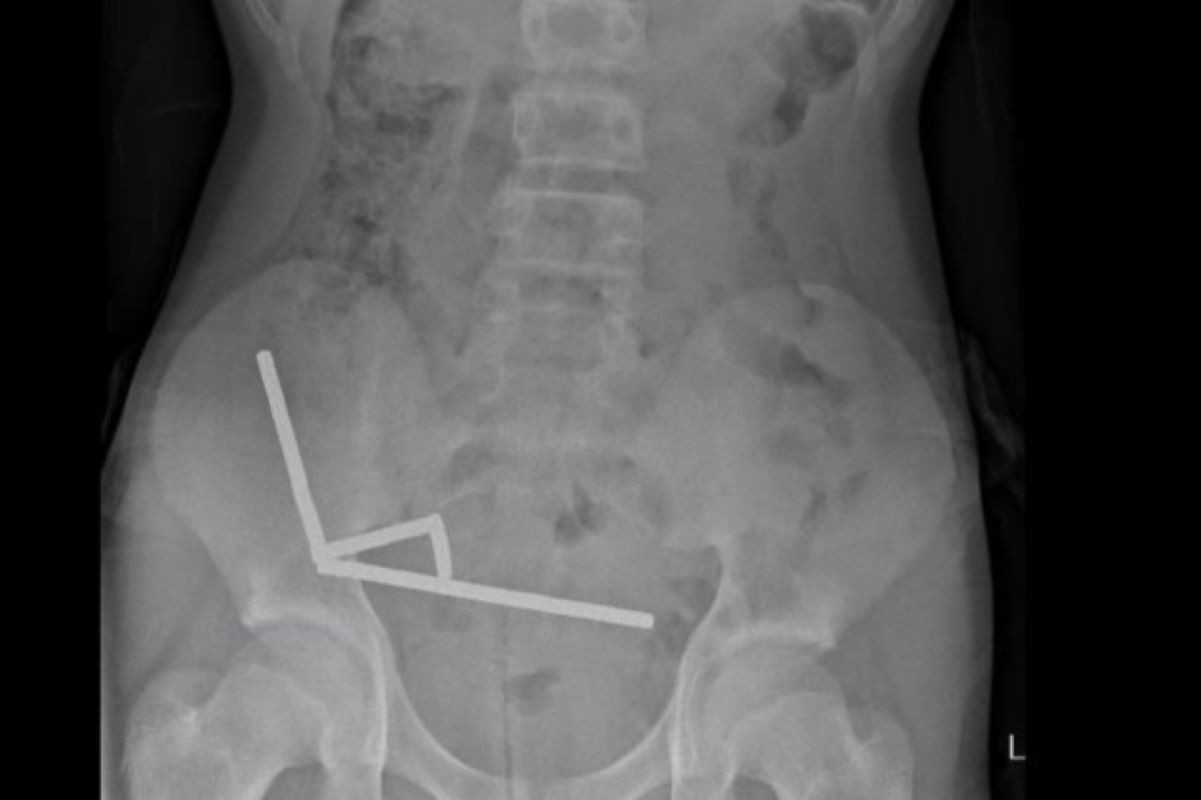

Recentemente, um caso alarmante envolveu um adolescente que ingeriu mais de 80 ímãs, resultando em necrose intestinal devido à pressão gerada pela atração magnética entre eles. Esse incidente reforça a gravidade das complicações associadas ao consumo de ímãs, especialmente em crianças e jovens.

Quando múltiplos ímãs são ingeridos, eles podem se atrair através das paredes do intestino, comprimindo tecidos e vasos sanguíneos. Além disso, a pressão prolongada (como ocorreu no caso mencionado) leva à necrose, onde partes do órgão são destruídas e podem exigir remoção cirúrgica.